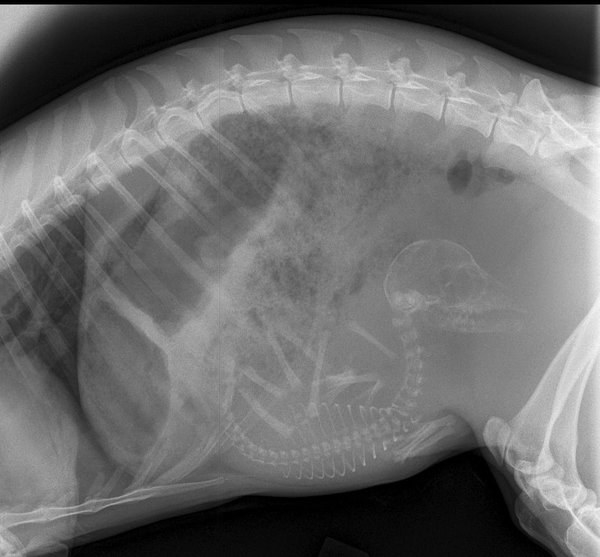

而現在,這17張動物懷孕X光照會讓你想大喊一聲:「天呀!」

3. 貓咪。